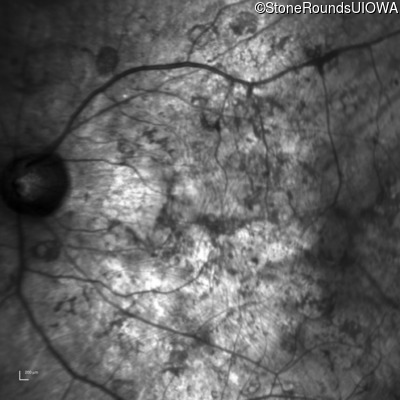

Infrared Fundus Photograph - Right - Hand Motion

Exemplar